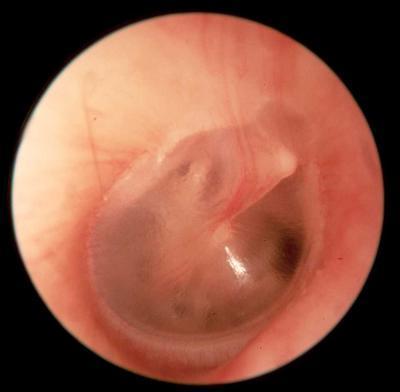

Question 1

Question

Describe the ear!

Answer

Bulging Tympanic Membrane

Acute Otitis Media

Distorted cone of light

Left ear

Treat with penicillin, amoxycillin, co-amoxiclav

Caused by: Streptococcus pneumoniae, haemophilus influenzae, moraxella catarhalis, GAS or S. aureus